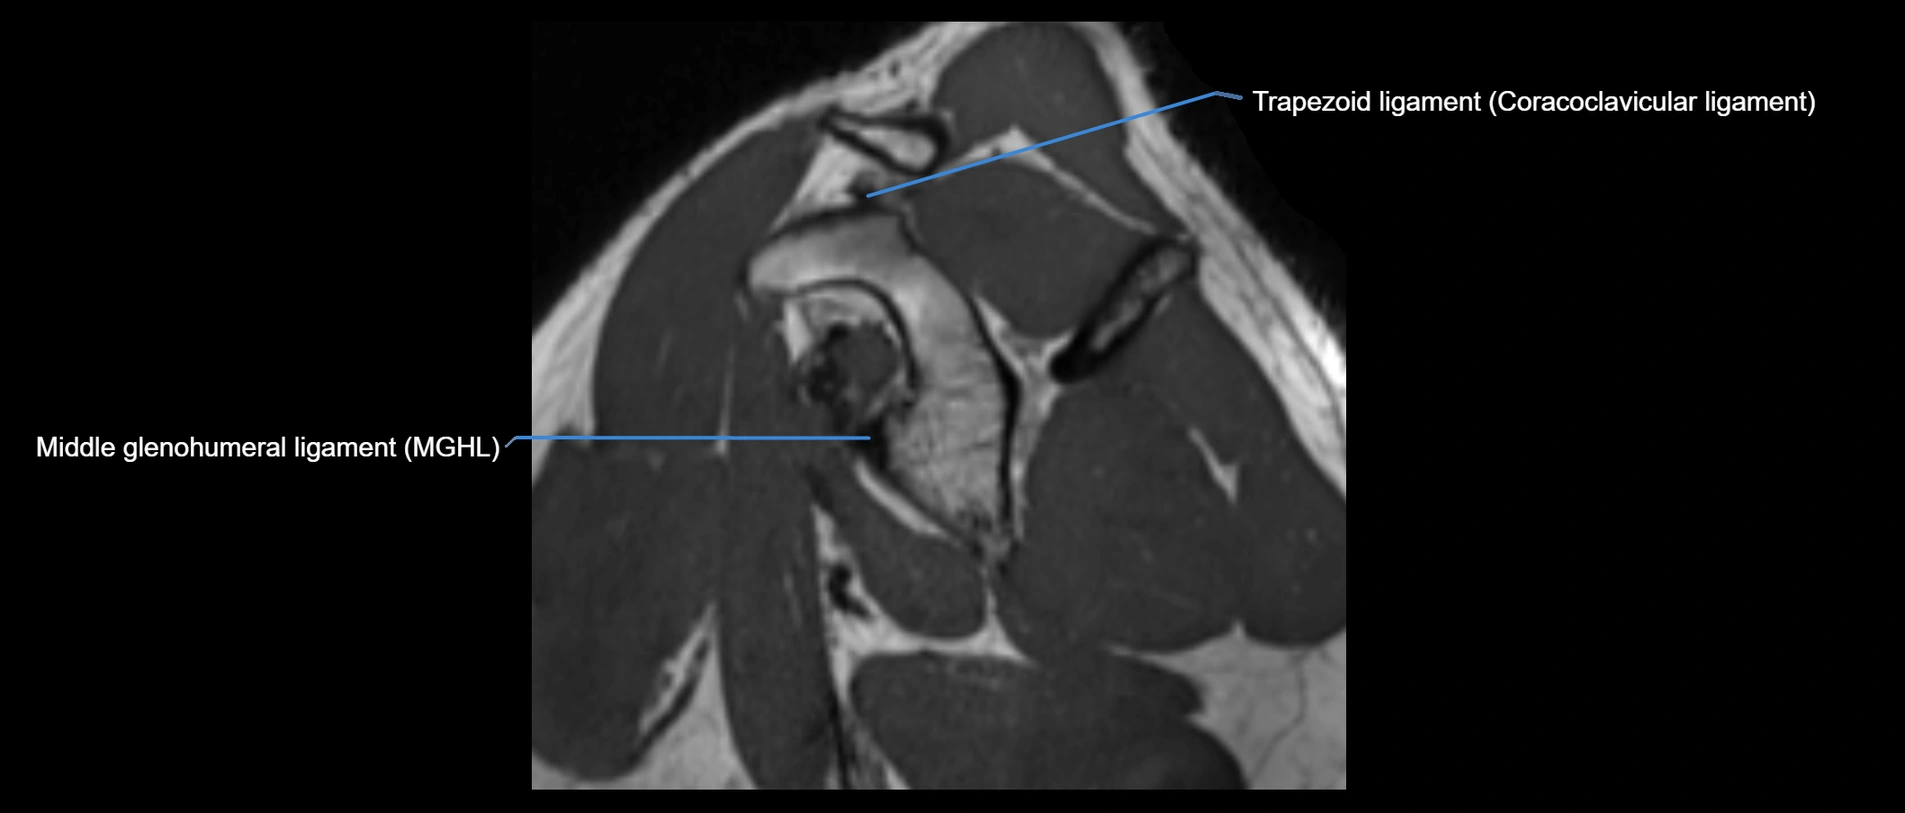

MRI images

image